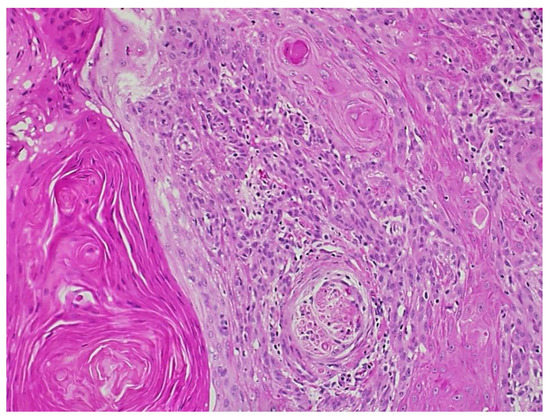

Figure 5.

Squamous cell carcinoma with perineural invasion of greater than 0.1 mm.

Ten months after Mohs surgery, the patient presented with a 2.4 cm fissured, indurated, erythematous, ulcerated plaque on the right ventral ulnar palm. (Figure 4) This was separated by 2.6 cm of normal skin from the scar from the prior C-SCC on the right hand. Punch biopsy revealed squamous cell carcinoma with perineural invasion involving a 0.1 mm cutaneous nerve. (Figure 5) With her scar contracture and functional impairment in that hand, she was referred to orthopedic oncology. After discussion of risks and benefits for excision with secondary intent healing versus a ray resection, the latter was agreed upon.